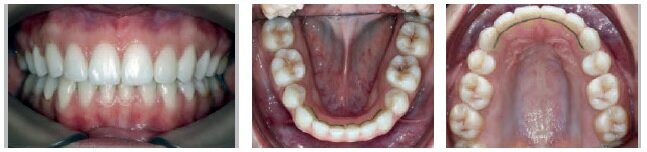

CASE NO 1

T.F. was 13 years old at the time of his first visit

Diagnosis

Class I, incisal-canine crowding in both arches

Class II long face syndrome, hyperdivergent

Retrusive chin

Presence of wisdom teeth buds

VISIT NO 6: POST-RETENTION PHOTOS +12 MONTHS